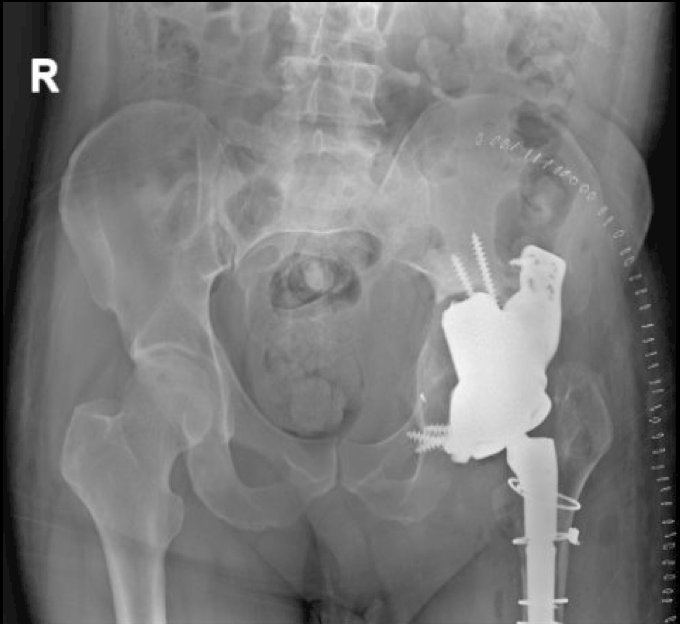

October 2022:

- Age: 48 years

- Reports pain

- Follow-up scheduled for 2023.